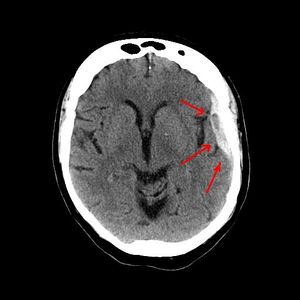

Appearance on CT | Biconvex lens | Crescent-shaped |

يعتمد رئيساً على تصوير الدماغ (التصوير الطبقي المحوري والرنين المغنطيسي MRI)، وفيه يظهر النزف عادة على شكل تجمع هلالي بين الجمجمة والدماغ.